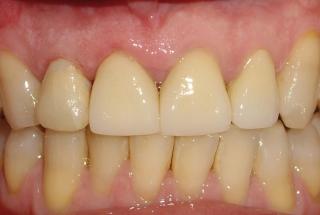

Clinical cases

MPI closely monitors clinical cases in the market to ensure their correct functioning and successful outcome.